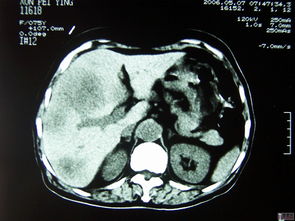

对于肝癌,B超有其典型的影像学表现,如低回声或混合回声团块、边界不规则、周边有声晕、内部血流信号丰富(“快进快出”的增强模式在超声造影中更明显)等。对于直径超过1-2厘米的肝癌结节,B超具有较高的检出率。

分辨率限制:对于直径小于1厘米,特别是小于5毫米的微小肝癌,常规B超容易漏诊。

位置与干扰:位于肝膈顶部、右叶深部或被肺部气体、肋骨遮挡的病灶,可能显示不清。

背景影响:在重度脂肪肝、肝硬化等背景下,肝脏整体回声不均匀,可能掩盖小病灶或使良恶性结节的鉴别变得困难。

B超发现肝脏实性结节:无论AFP是否正常,均不能掉以轻心。下一步的关键是进行多期动态增强影像学检查,这被认为是无创诊断肝癌的“金标准”。

增强CT/MRI:通过观察病灶在动脉期、门脉期和延迟期的强化特征(典型的HCC表现为“快进快出”——动脉期明显强化,门脉期或延迟期强化消退),可以极大提高诊断的准确率。MRI对于小肝癌和肝硬化结节的鉴别能力通常优于CT。